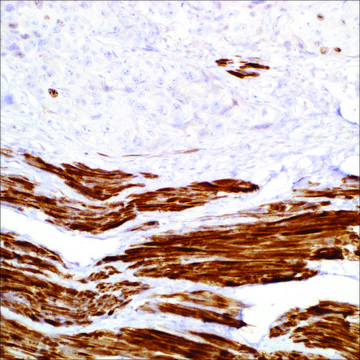

bladder, leiomyoma

Smoothelin is a constituent of the smooth muscle cell cytoskeleton protein exclusively found in differentiated smooth muscle cells (SMC). Cells with SMC-like characteristics, such as myofibroblasts and myoepithelial cells, as well as skeletal and cardiac muscle do not contain smoothelin. To distinguish bladder muscularis mucosae (MM) from muscularis propria (MP) muscle bundles is crucial for accurate staging of bladder carcinoma. Strong smoothelin expression is nearly exclusively observed in muscularis propria. Therefore, the staining pattern of MP (strongly positive) and MM (negative or weakly positive) makes this technique an attractive diagnostic tool for the sometimes difficult task of staging bladder urothelial carcinoma, such as in transurethral resection specimens of urinary bladder tumors. Differentiating between smooth muscle tumors and other mesenchymal neoplasms of the GI tract can be challenging in small biopsies. Anti-smoothelin immunostaining can be helpful in differentiating benign (+) from malignant smooth muscle tumors (-), and other mimics(-).